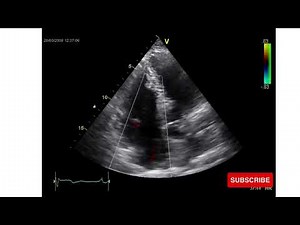

Ebstein Anomaly on Echocardiography

YouTube

Dr. M Usman Javed

已浏览 1.6万 次

2024年3月3日

Ebstein Anomaly | Congenital Heart Disease | Echo

Cardiology Insight

已浏览 768 次

2022年9月20日

Echo - Ebstein Anomaly

已浏览 620 次

2019年8月13日

Joy to the World

Ebstein's Anomaly - Transthoracic Echocardiogram (TTE)

已浏览 1.5万 次

2013年3月6日

medicaldump